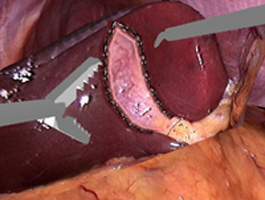

The virtual abdominal model consists of a photographic texture made from composited frames taken from actual video footage of a laparoscopic cholecystectomy. The texture is mapped onto a simplified geometry

Figure 1) Panoramic Image of Abdominal Cavity, made from composited Endoscopic Images

Figure 2) Simulation of Cauterization of Gallbladder Border.